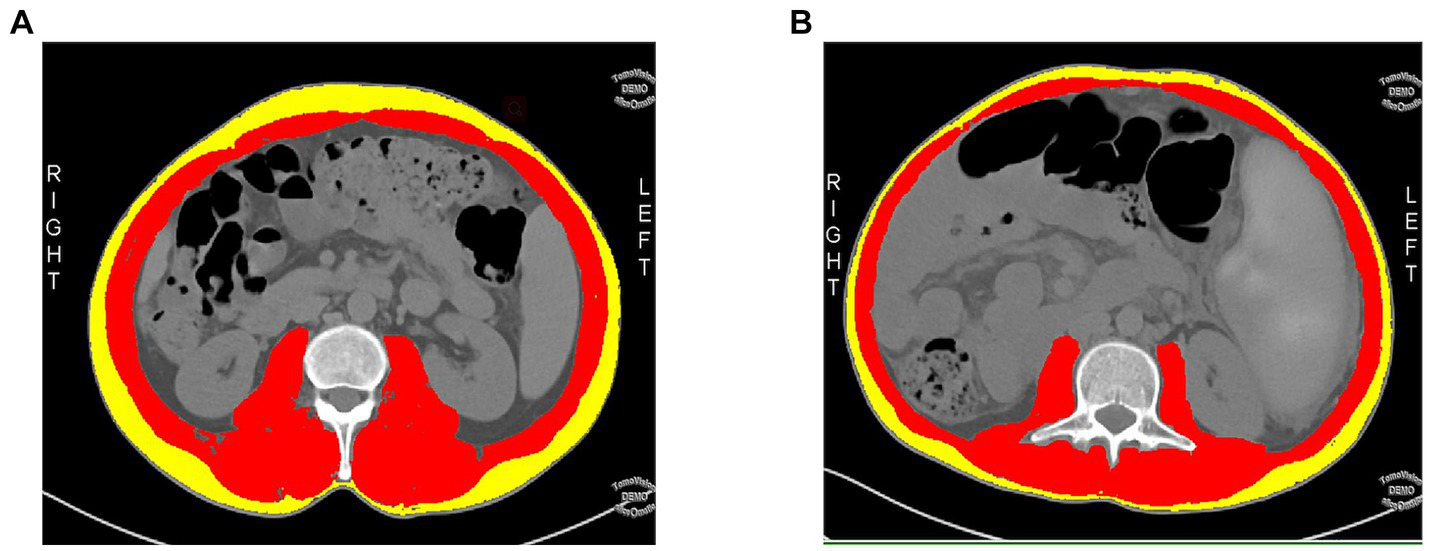

The Slice-O-Matic software (5.2.1 version, https://tomovision.com/) was used to semi-automatically identify the entire abdominal wall muscles at the maximum level of the L3 according to the threshold of −29 to 150 HU, and the subcutaneous fat according to the threshold of-30 to-190 HU, respectively. After determining the internal and external contours of the muscles, they were separated from the subcutaneous fat and abdominal fat. Any misidentified areas in the images were corrected by manual adjustment. The subcutaneous fat area (SFA, cm2), skeletal muscle area (SMA,cm2), and skeletal muscle density (SMD, HU) of the abdomen were automatically calculated and obtained (25). For details, see Figure 2. This work was completed by radiologists (reader1and reader2) with experiences in diagnostic abdominal imaging, and the average of their two measurements was taken. The endoscopy results were not shared with the two radiologists.

Figure 2

A cross-sectional abdominal skeletal muscle area (SMA, cm2; red areas), surrounding subcutaneous fat area (SFA; yellow areas) and skeletal muscle density (SMD, HU) were measured on abdominal cross-sectional MDCT images at the maximum level of the third lumbar vertebra(L3) using sliceomatic software. (A) A 48-year-old male patient with a decompensated cirrhosis without upper gastrointestinal bleeding(UGIB), SMA = 148.9 cm2, SFA = 68.09 cm2, SMD = 47.99HU. (B) A 49-year-old male patient with decompensated cirrhotic patient with UGIB, SMA = 115 cm2, SFA = 38.28 cm2, SMD = 41.53HU.